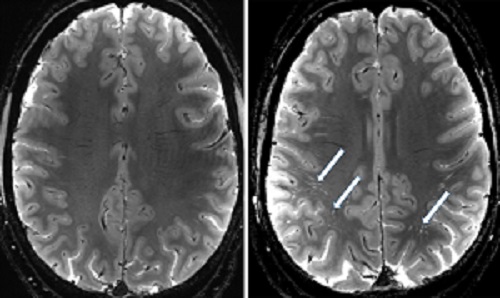

“The 7T is helping us uncover novel information about so-called mild traumatic brain injuries,” Whiting said. “Typically, a patient with a head injury arrives at the Emergency Department and receives a CT scan which shows if there is any bleeding in the brain, but the 7T shows even more detail,” he said.

Most glymphatic research is conducted on animals but there continues to be a movement toward more accurately classifying brain injuries in humans, Whiting said. “One of the hopes is people will realize mild traumatic brain injury is a misnomer. Yes, they are mild compared to life-threatening brain injuries. But there are structural changes occurring in the brain after these mild injuries, and this can’t be seen with conventional imaging techniques.”

By building a registry of patients who experienced traumatic brain injury, the team can track individuals over time and see the changes in the brain from its early stages. “One of the most surprising findings is how quickly we are seeing changes in the brain after a head injury. The perivascular spaces that make up the glymphatic system enlarge rapidly, sometimes within hours of injury. This may help the brain eliminate harmful waste products. But in people who have experienced multiple head injuries, this response seems to be diminished.”